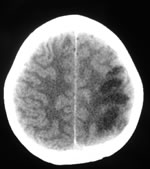

La ripetizione della TAC (Fig. 1) dopo alcuni giorni ha messo in evidenza alcune aree ipodense a sx, a livello parietale e temporo-mandibolare, che non presentano enhancement dopo mezzo di contrasto, dato che esclude un tumore o un ascesso. Finalmente esegue angio-RMN (Fig. 2) che mostra una occlusione della carotide interna in un quadro suggestivo di dissezione della carotide interna. A quel punto viene rivalutata la storia e ripete l'eco-doppler dei vasi del collo (Fig. 3 e Fig. 4) che mostra un ostruzione della carotide interna di sinistra ad 1 cm dalla biforcazione, senza alterazioni a destra. Il recupero del bambino è stato quasi completo.

Eco-doppler della carotide sinistra: ostruzione ad 1cm dalla biforcazione